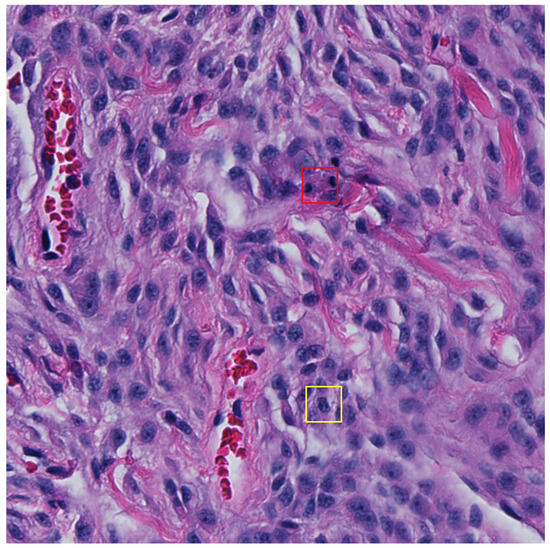

Figure 5. An example 512 × 512 pixel image from the test set with a false negative (FN) shown in the red bounding box and a false positive (FP) detection shown in the yellow bounding box (32 × 32 pixels). The FP detection provides a probability confidence score of 5.3% and so would typically be dismissed as a mitosis candidate once the adaptive F1-score threshold is applied.

Multi-stage (typically dual-stage) approaches have also become increasingly prevalent over the years where they typically take the form of selecting mitotic candidates in the first stage and then apply another classifier in the second stage [32,33,47,48,49]. Although not reflected in the main findings of this study, we attempted to use a second-stage classifier (Figure A1) on mitotic candidates to classify between TP and hard FPs to no avail (see results of the two-stage approach in Table A8 and its subsequent ROC curves in Figure A2). Most machine learning methods require large datasets for effective training, which in this case was not available once optimisation was applied using the adaptive F1-score threshold method. One could train models using the non-thresholded detections; however, this would result in a model that is able to distinguish between true positive mitosis and mostly obvious FP candidates. By applying the adaptive F1-score thresholding method, we constrained the dataset and attempted to learn differences between TP and high confidence hard false positive detections, but we did not provide an adequately large dataset for training. Figure 5 depicts a 512 × 512 pixel image in the test set, highlighting FN and FP detection.